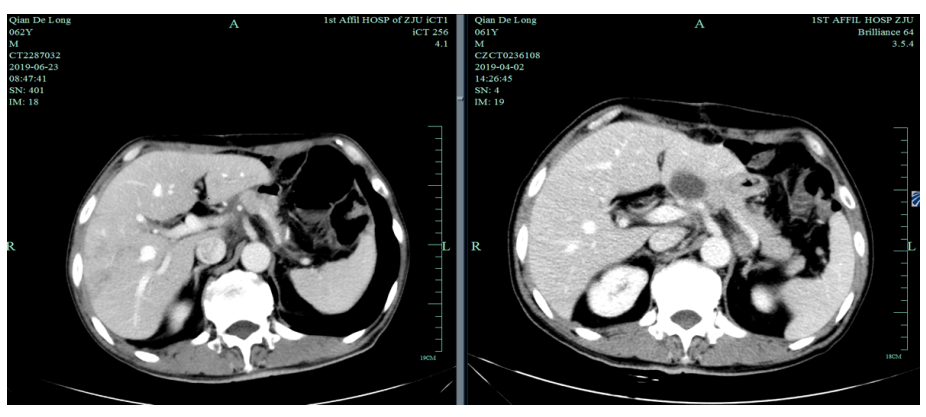

入我院后全面进行评估(2019.4):全腹部CT平扫+增强评估提示腹膜后,胰腺周围多发淋巴结增大,淋巴结转移考虑。

2019-4-2至2019-6-5行SOX+赫赛汀 q3w 4周期联合化疗:具体为奥沙利铂220mgD1、替吉奥3# BID D1-14、赫赛汀400mg(首次)+300mg。

一线化疗疗效评估(2019.6 vs 2019.4):胃癌术后改变。影像评估CR。